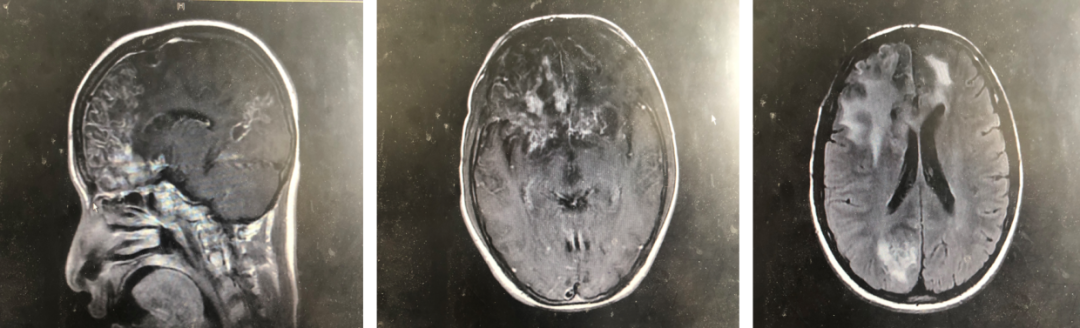

2019年6月2日,阿文求医到华山医院,先来到急诊,做了头颅MRI示:大脑额叶、颞叶多发病变灶伴有脑膜异常强化。做了腰穿,脑脊液检查见:WBC 488*10^6/L,多个核4%,单个核96%,RBC 216*10^6/L,葡萄糖 2.1mmol/L,氯 108 mmol/L,蛋白 4705mg/L。并将脑脊液送检病原学检测及二代测序检查。当时予以美罗培南+利奈唑胺经验性抗感染治疗。

图1. 头颅MRI增强

结合病史和检查,陈教授和毛医生初步考虑阿文为中枢神经系统感染,但病原目前尚不能确定。常见感染性疾病包括化脓性脑炎、病毒性脑炎、结核性脑膜炎、真菌性脑膜炎等。阿文头颅MRI可见明显的环形增强灶,脑脊液提示WBC增高、蛋白水平升高,糖和氯的水平轻度下降,病程进展较快,考虑化脓性脑炎不能排除。但证据不充分,且有一定程度的反证据,比如白细胞比例以淋巴细胞为主,强化抗细菌治疗效果不佳。